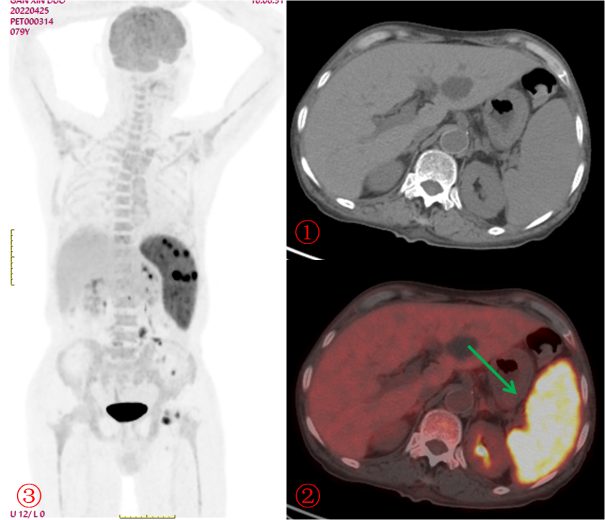

老年男性,發(fā)熱半月,全身CT未見確切異常。PET/CT示脾臟增大伴代謝明顯不均質(zhì)增高(圖2?綠箭),腹盆腔部分略大淋巴結(jié)伴帶代謝增高,診斷為淋巴瘤,病理證實(shí)為小B細(xì)胞淋巴瘤。